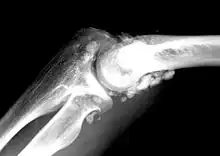

| X-ray of an elbow affected by synovial chondromatosis | |

Synovial chondromatosis is a locally aggressive bone tumor of the cartilaginous type.[1] It consists of several hyaline cartilaginous nodules and has the potential of becoming cancerous.[1]